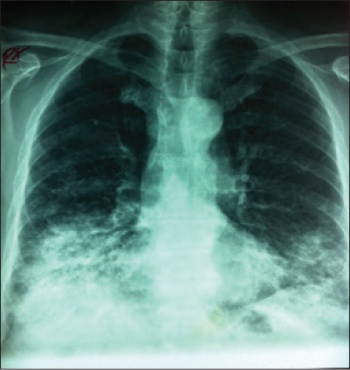

Figure 2. Repeat CXR one week later

Figure 2. Repeat CXR one week later(click to enlarge)

However, he continued to deteriorate radiologically, his CXR seven days from admission (see Figure 2) showed more patchy infiltrates on the right side with extension onto the left lung.